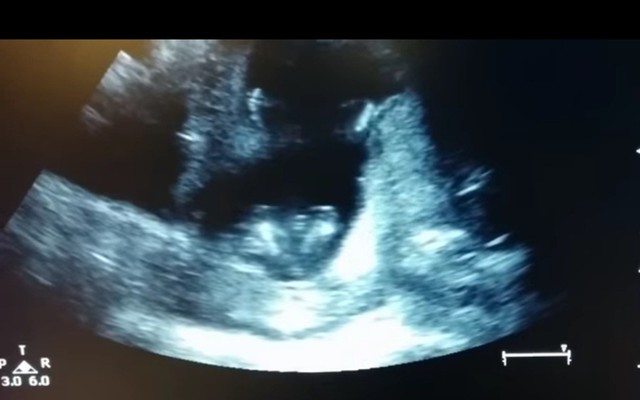

thai nhi 14 tuần tuổi

Thai nhi 4 tháng tuổi vỗ tay trong bụng mẹ

Tri thức mới 2015-03-30T20:30:00Khi mẹ của thai nhi hát cùng các bác sĩ trong bệnh viện, em bé đã vỗ tay theo nhịp điệu.